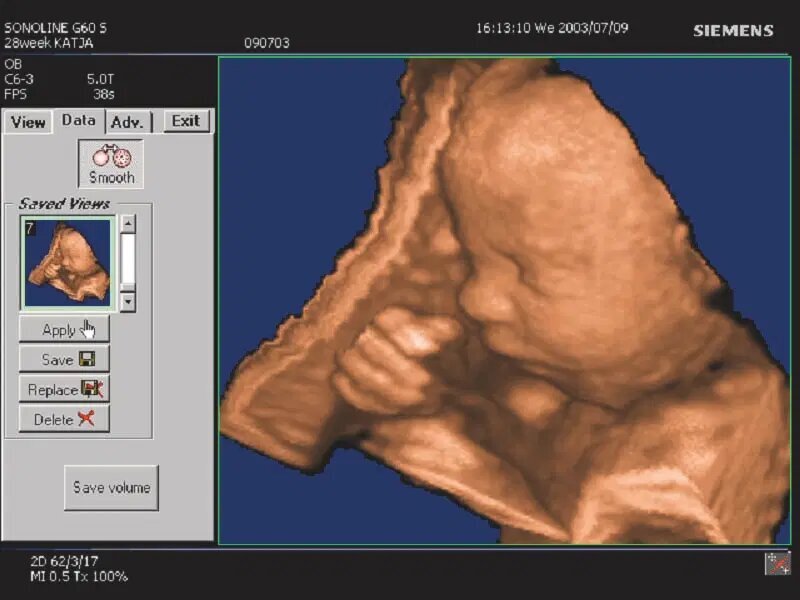

نرمافزار "۳-Scape Real-Time ۳D" اولین نرمافزار زمان واقعی سه بعدی با وضوح بالا؛ که اجازه پردازش و نمایش تصاویر سه بعدی از ویژگیهای آناتومیک را فراهم میساخت. این امر در سونوگرافی جنین بسیار مفید است، زیرا حرکات جنین معمولاً مانع تشخیص دقیق میشود.

اختراع فناوری تصویربرداری اولتراسوند چهار بعدی؛ برای اولین بار امکان نمایش بلادرنگ تصاویر سه بعدی را فراهم کرد و تصاویر متحرک را در اختیار پزشکان قرار داد و اطلاعات تشخیصی موجود، در بخش زنان و زایمان، تصویربرداری از ناحیه دامین و عروق، را افزایش داد.